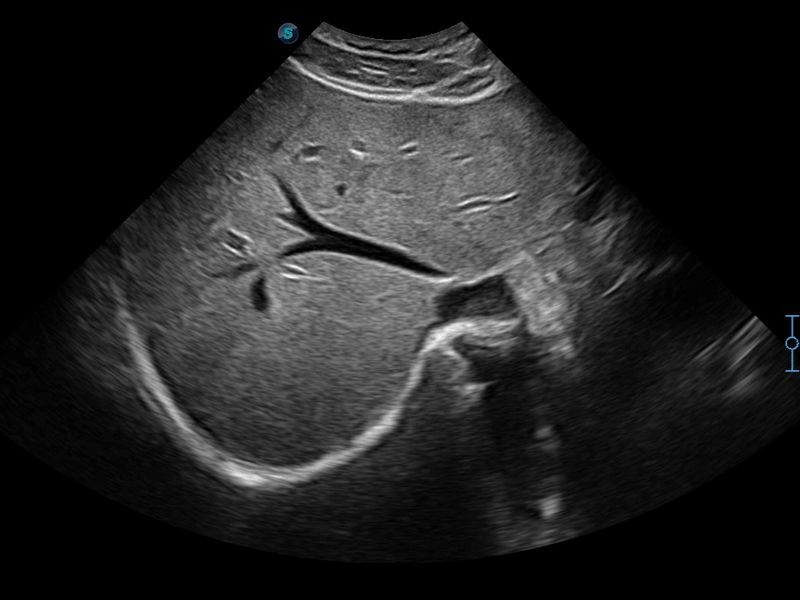

μ-Scan+新一代微米成像技术

新一代微米成像技术大大提高了器官和病变的可见性。高清对比度分辨率将抑制斑点噪声,同时保持真实的组织结构。